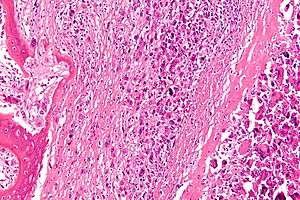

A bone tumor (also spelled bone tumour) is a neoplastic growth of tissue in bone. Abnormal growths found in the bone can be either benign (noncancerous) or malignant (cancerous).

Malignant primary bone tumors include osteosarcoma, chondrosarcoma, Ewing's sarcoma, fibrosarcoma, and other types.